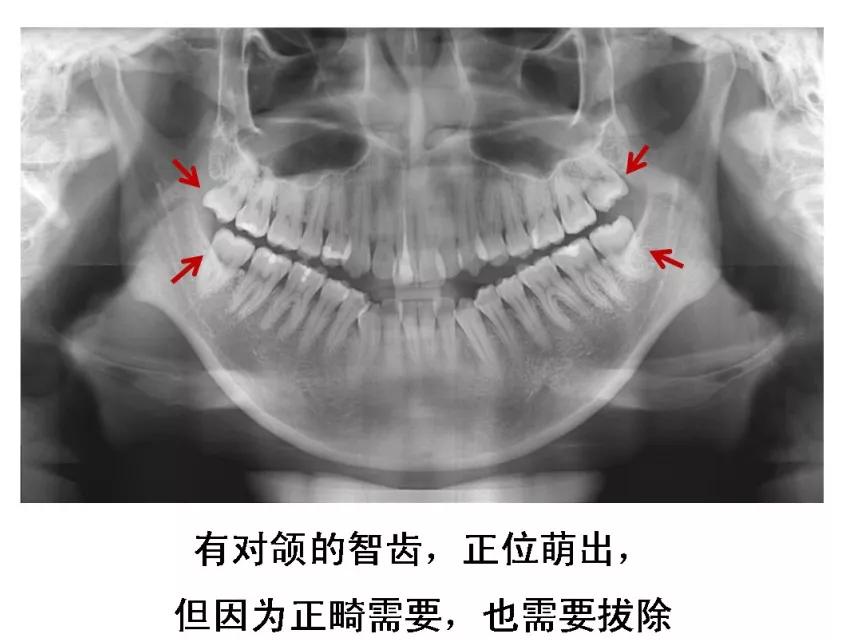

6、牙齿需要矫正,以及在12-16岁做过矫正的小朋友 ,需要根据正畸医生的建议,及时拔除智齿,以获得完美的牙列和脸型!